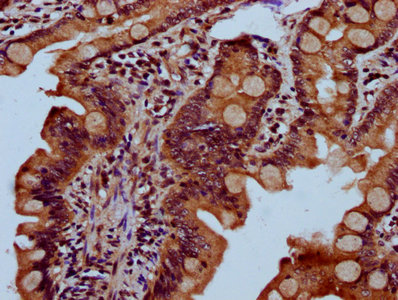

IHC image of CSB-PA621874LA01HU diluted at 1:300 and staining in paraffin-embedded human small intestine tissue performed on a Leica BondTM system. After dewaxing and hydration, antigen retrieval was mediated by high pressure in a citrate buffer (pH 6.0). Section was blocked with 10% normal goat serum 30min at RT. Then primary antibody (1% BSA) was incubated at 4°C overnight. The primary is detected by a biotinylated secondary antibody and visualized using an HRP conjugated SP system.

IHC image of CSB-PA621874LA01HU diluted at 1:300 and staining in paraffin-embedded human appendix tissue performed on a Leica BondTM system. After dewaxing and hydration, antigen retrieval was mediated by high pressure in a citrate buffer (pH 6.0). Section was blocked with 10% normal goat serum 30min at RT. Then primary antibody (1% BSA) was incubated at 4°C overnight. The primary is detected by a biotinylated secondary antibody and visualized using an HRP conjugated SP system.